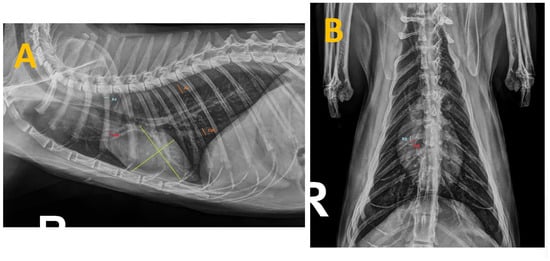

Thoracic radiographs from all cats were taken using the same radiographic equipment (Bennett HFQ-600P, Greensboro, NC, USA) during inspiration and without sedation to minimize changes in heart size [24]. Views were obtained in both right laterolateral and dorsoventral projections, and radiographic measurements were taken using adjustable calipers by an unbiased operator (SFC), who has 10 years of clinical experience in cardiorespiratory diseases in small animals and was blinded to the clinical status of the study cats (Figure 1).

Figure 1. Thoracic radiographs of a cat seropositive for anti-Dirofilaria-immitis antibodies and presenting with clinical signs. The measurements taken during this study are shown as follows: (A) Right laterolateral projection illustrating the measurements of the caudal vena cava (CVC) and aorta (Ao) (in orange), the fourth rib (R4) (in blue), the right cranial pulmonary artery (CrPA) (in red) and the vertebral heart score (in green). (B) Dorsoventral projection displaying the measurement of the right caudal pulmonary artery (CdPA) (in red) in relation to the ninth rib (R9) (in blue).

In lateral recumbent radiographs, the Vertebral Heart Score (VHS) measurement was obtained from the sum of the short-axis and the long-axis measurements as previously described [25]. The cardiac long axis was obtained from the cardiac apex to the base of the heart where it meets the trachea just cranial to the carina, expressed as the number of vertebral lengths in the lateral radiograph, measured caudally from the cranial border of T4. The short axis of the heart was measured perpendicular to the long-axis measurement at the point of maximum heart width, expressed as the number of vertebral lengths in the lateral radiograph, measured caudally from the cranial border of T4 [26].

In the laterolateral projection, the diameter of the right fourth rib (R4) just below the spine and the greatest diameter of the caudal vena cava (CVC) were also measured as described in previous studies, which included dogs with heartworm, in order to determine the mean caudal vena cava size, expressed as a ratio of the diameter of R4 [27,28,29]. The measurement of the diameter of the descending aorta (Ao) at the same intercostal space as the CVC was carried out as well, following previous guidelines in dogs [29]. Next, the CVC/Ao and CVC/R4 ratios were established.

Other radiological measurements were taken, including the diameter of the right cranial pulmonary artery (CrPA) passing through R4 in the laterolateral projection and the diameter of R4 at a point just distal to the spine. Moreover, in the dorsoventral projections, the distal and left sides of the summation shadow created by the right caudal pulmonary artery (CdPA) with R9 were measured. Finally, the CrPA/R4 and CdPA/R9 ratios were calculated from these measurements [30].